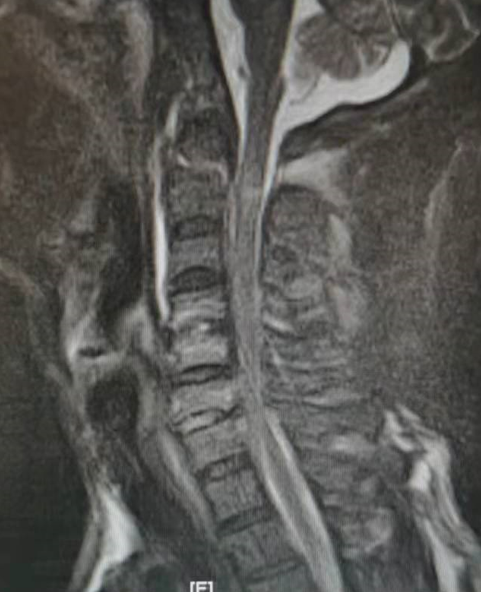

入院后,福建医科大学附属第一医院下派脊柱外科专家朱希田副主任医师立即查看了患者的病情,考虑患者枢椎齿状突骨折伴寰椎后脱位致高位颈脊髓损伤可能性较大,如果不尽早手术,将引起颈脊髓损伤继续加重,并可导致高位截瘫可能。朱希田副主任医师立即将病情汇报医院领导,开通核磁共振检查绿色通道,进一步明确患者病情。

然而,该项颈椎手术技术难度高,风险较大,尤其是高位寰枢椎骨折脱位手术为脊柱手术的最难区域,该区域为头颅和颈椎的结合部,毗邻高位延髓生命中枢以及椎动脉等脑供血动脉,解剖结构变异较大,稍有不慎,将引起延髓生命中枢损伤或椎动脉损伤,从而导致心脏呼吸功能障碍、严重的四肢瘫痪、甚至死亡。

朱希田副主任医师组织科室医护团队进行了详细的讨论分析,决定先予俯卧位行“后入路寰枢椎骨折切开复位+椎弓根钉内固定术”,再仰卧位行“前入路颈4-5、颈5-6、颈6-7椎间盘切除+颈椎管减压+颈椎椎间植骨融合+颈4-颈7椎体钛板螺钉内固定手术”。